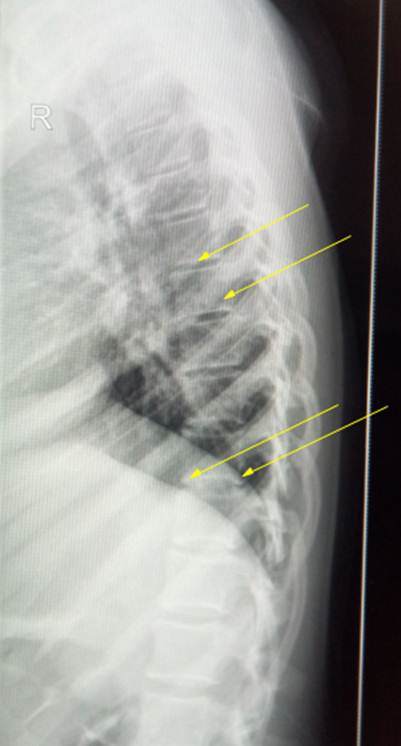

Боковая

рентгенограмма позвоночника ребенка 13 лет, на ней видна развернутая картина

поражения грудного отдела юношеским остеохондрозом. Наблюдаются хрящевые узлы,

вдающиеся в тела позвонков (обозначены зелеными стрелками), явления склероза

замыкательных пластинок вокруг узлов, а также фрагментарность и разорванность

апофизарных колец (желтые стрелки). Межпозвоночные пространства неравномерной

высоты, что свидетельствует о изменениях

в межпозвоночных дисках.